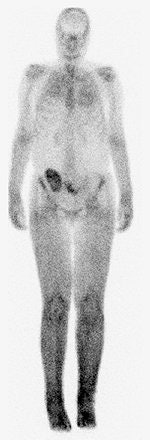

![]() |

| A 30-year-old woman with nephrogenic systemic fibrosis with predominant skin finding. Anteroposterior and lateral Tc-99m HDP delayed bone scan shows extensive symmetric skin uptake in lower extremities and distal upper extremities. Uptake is also seen in calf muscles, Achilles tendon, and chest wall. Broome DR, Girguis MS, Baron PW, Cottrell AC, Kjellin I, and Kirk GA, "Gadodiamide-Associated Nephrogenic Systemic Fibrosis: Why Radiologists Should Be Concerned" (AJR 2007; 188:586-592). |